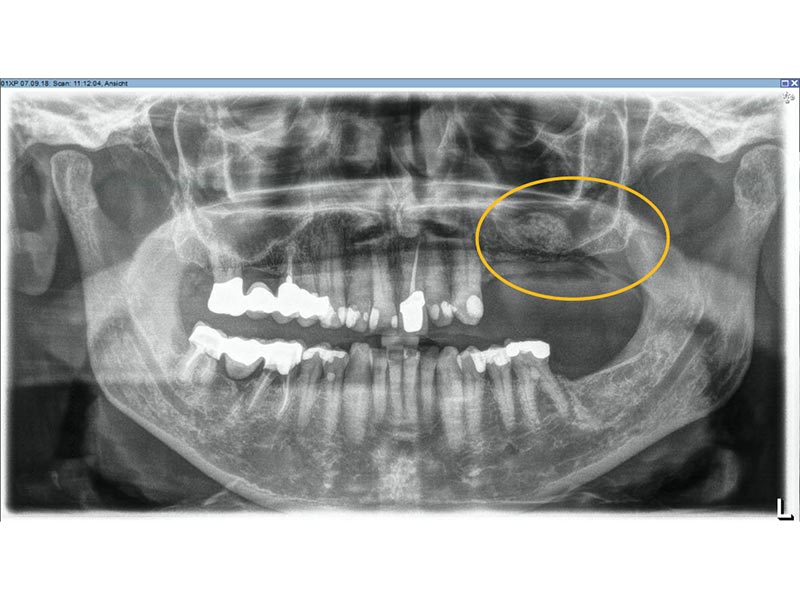

Unter dentalen Implantaten versteht man im allgemeinen eine Schraube, die dort, wo ein oder mehrere Zähne verloren gegangen sind, in den Kieferknochen "eingepflanzt" wird. Diese Therapieform der Implantologie hat sich in den letzten Jahren zu einem alltäglichen Therapieverfahren in der Zahnheilkunde entwickelt. Wissenschaftliche Untersuchungen zeigen hierfür eine Erfolgsquote von i. d. R. 80-98 % über 10 Jahre. Verglichen mit anderen zahnärztlichen Maßnahmen gibt es nahezu keine andere Therapie mit derart guten Erfolgsaussichten. Auch eine Verbesserung der Lebensqualität wird durch implantatgetragenen Zahnersatz laut klinischer Studien erreicht.

Mittlerweile hat sich die Implantologie zu einem alltäglichen Therapieverfahren mit sehr guten Erfolgsaussichten in der Zahnheilkunde entwickelt. Bei guter Mundhygiene und regelmäßigen Kontrolluntersuchungen können fachmännisch gesetzte Zahnimplantate ein Leben lang halten.